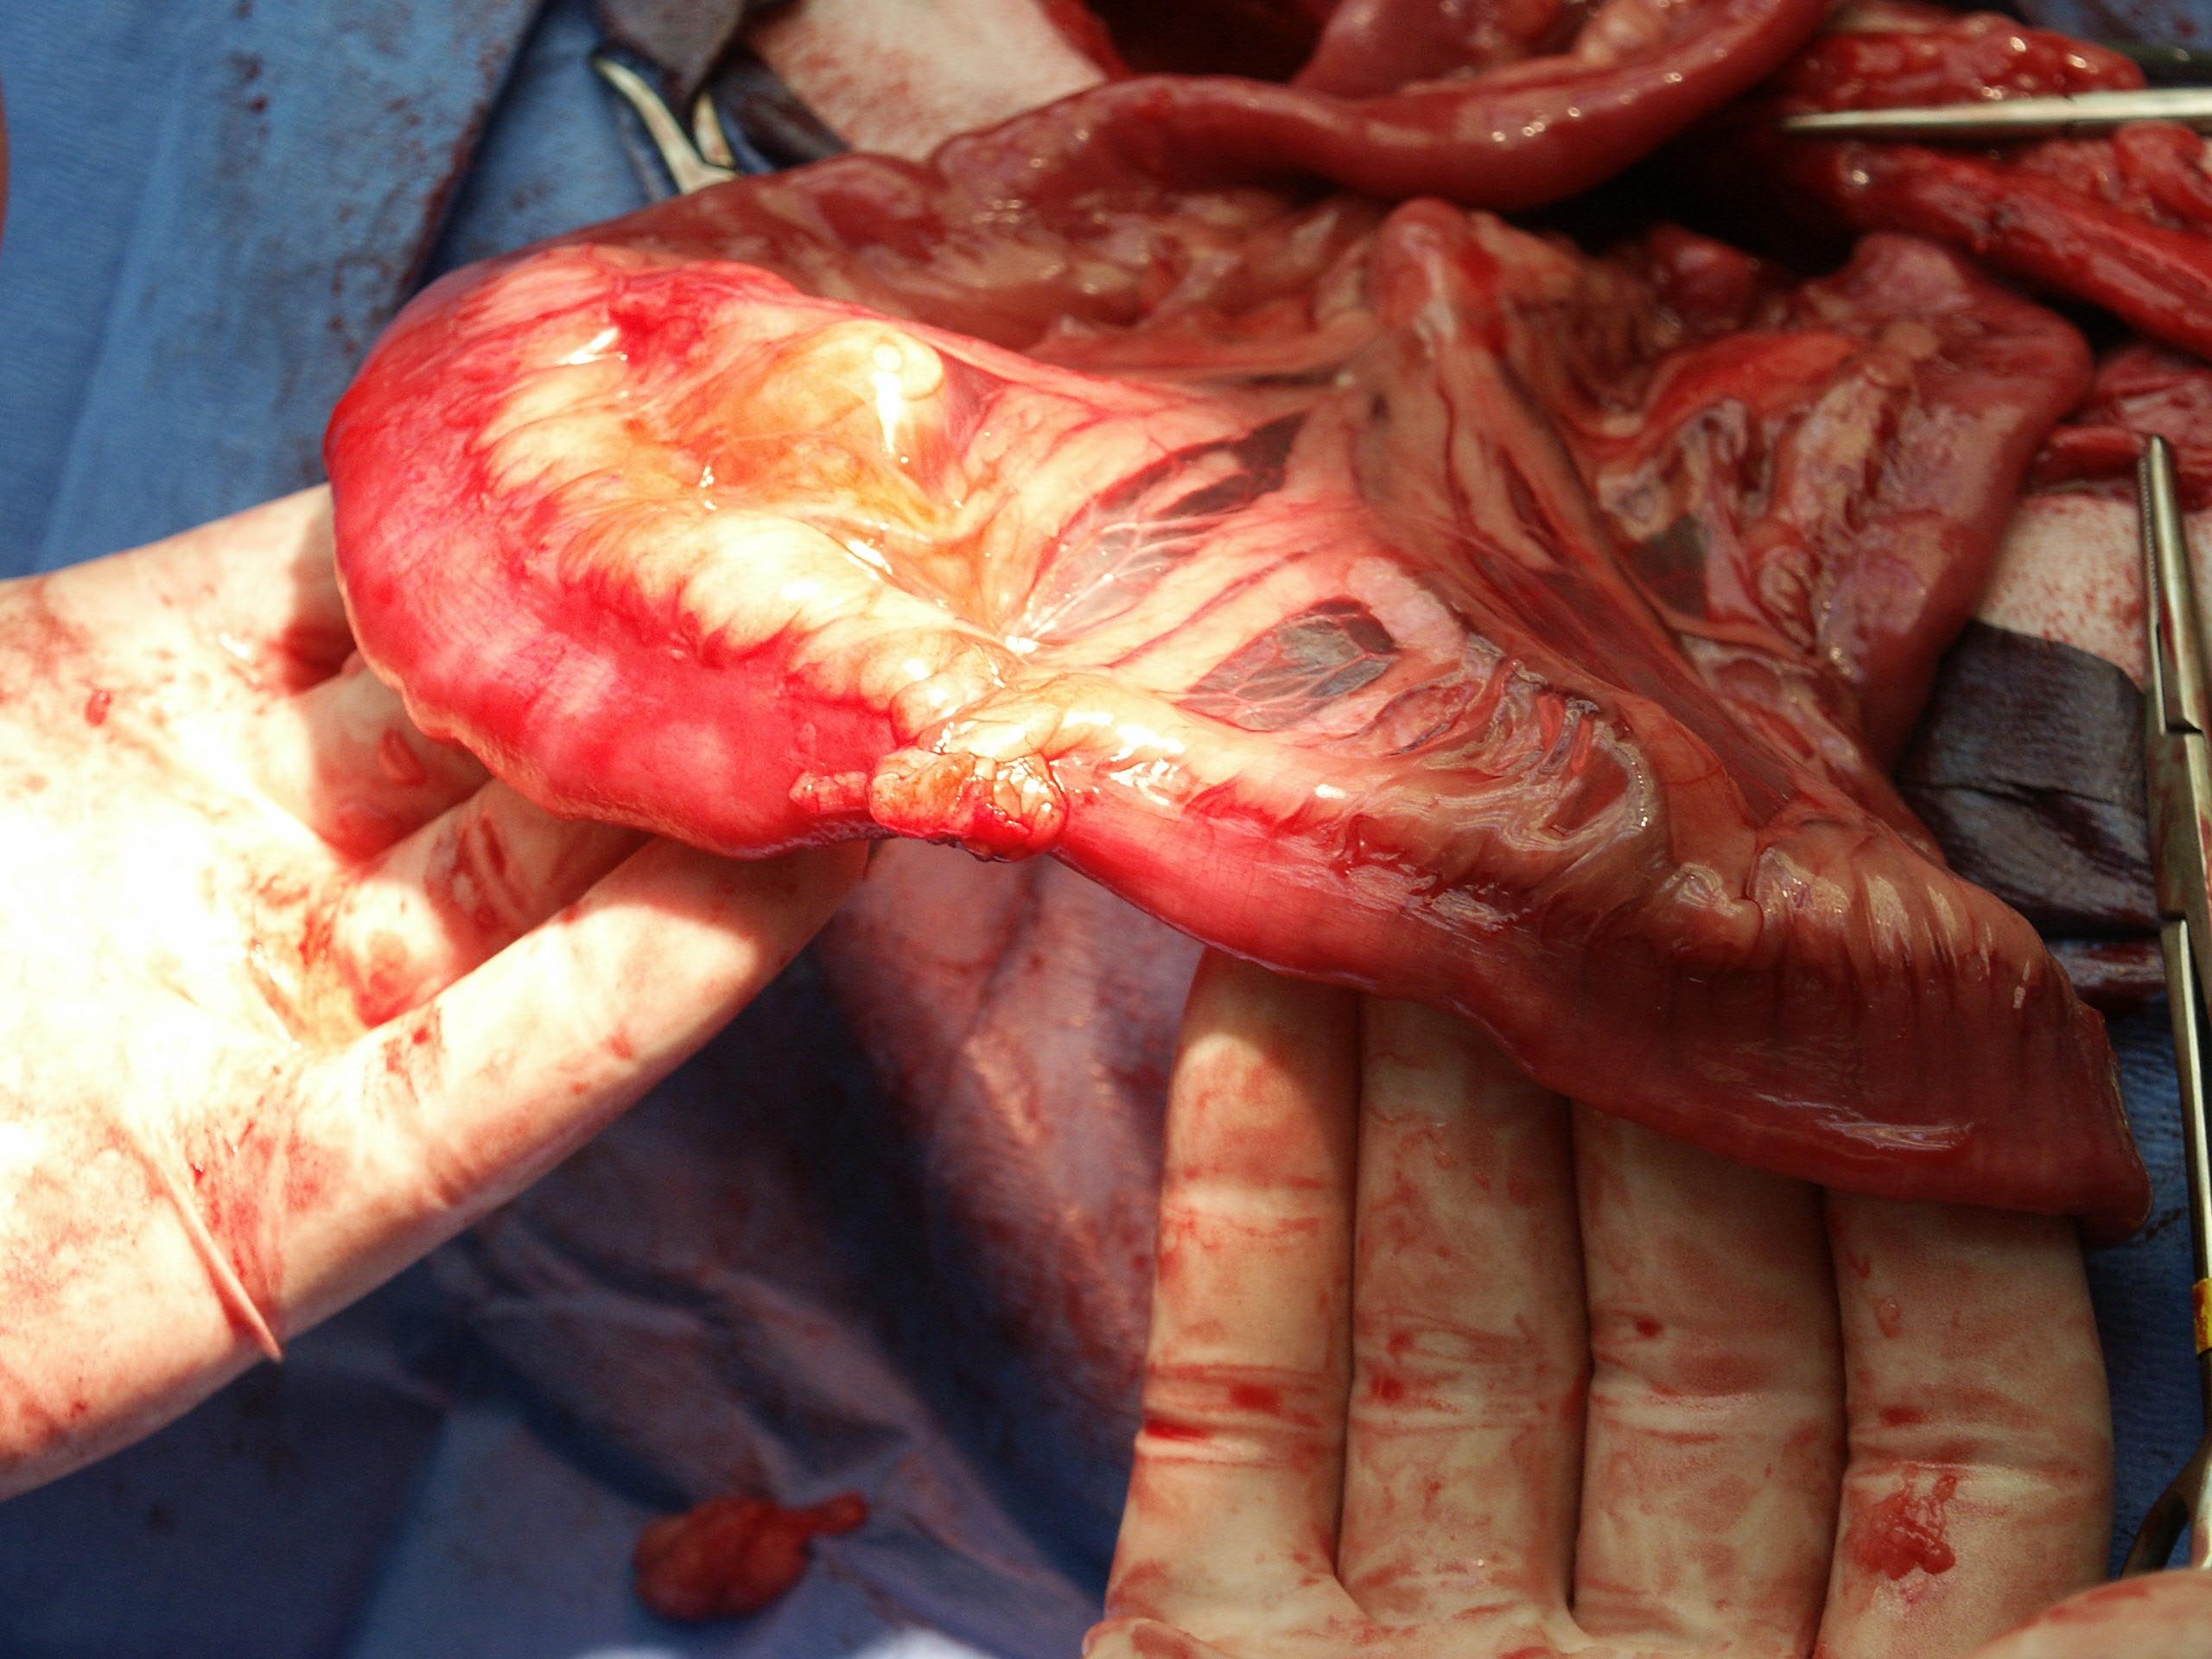

On exploratory laparotomy the intestines were attached to the abdominal wall creating a stricture (see photo) but a GI foreign body could not be found. Liberating the adhesion was enough to restore function and the patient recovered uneventfully.

Intestinal resection and likely anastomosis would be recommended. Foreign matter or focally compromised bowel could present in this manner, therefore intestinal biopsies of the compromised region would be ideal.